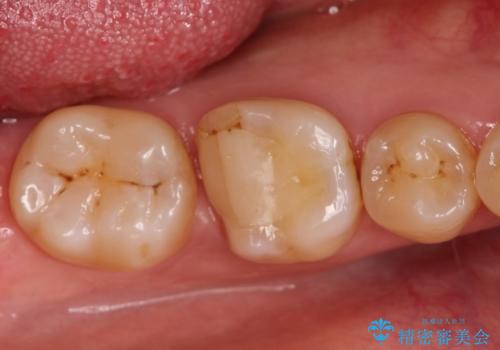

検査の結果、神経は保存不可能と診断されたため、根管治療~オールセラミッククラウンによる治療を行いました。

根管治療を行った歯は破折のリスクが高まるので被せものによる修復が必要になります。